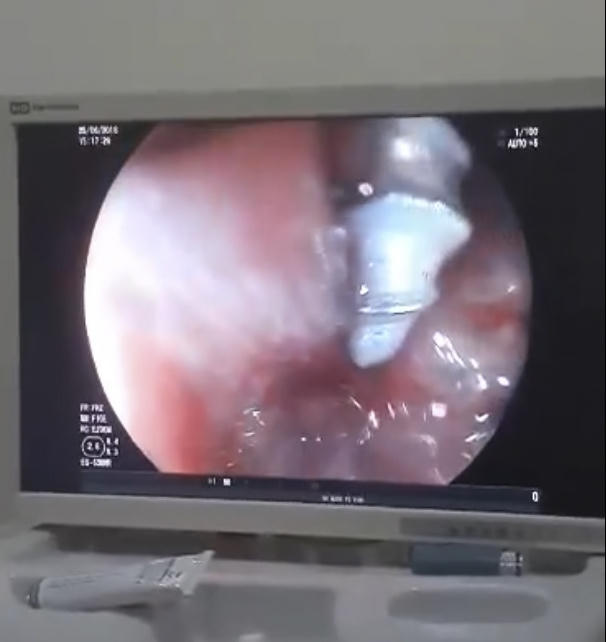

“Sau khi đặt máy xác định dị vật xuống sâu hơn ở D3 tá tràng so với phim X – Quang. Do dị vật có bề mặt xoắn ốc lại dài 3cm so với kích thước lồng ruột của trẻ 2 tuổi nên thủ thuật tiến hành rất khó khăn.

Sau 30 phút dị vật đã được lấy ra mà không có một tai biến nào. Kết quả kiểm tra lại niêm mạc tá tràng – dạ dày – thực quản không tổn thương, không chảy máu”, bác sĩ Phùng Thị Hằng – Trưởng khoa Nội người trực tiếp tiến hành thủ thuật cho biết.